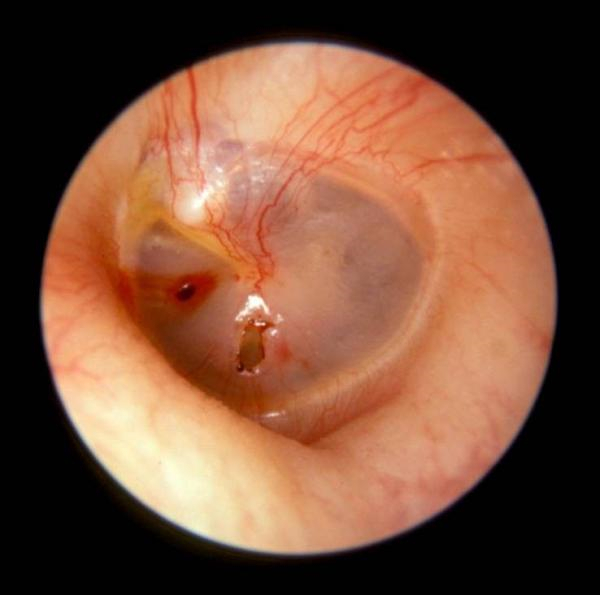

外傷性破裂鼓膜穿孔